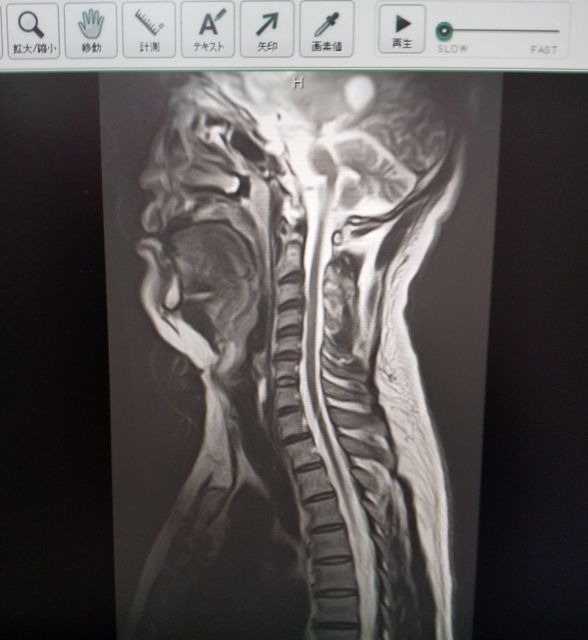

当院はエコー(超音波画像診断装置)設置院です。